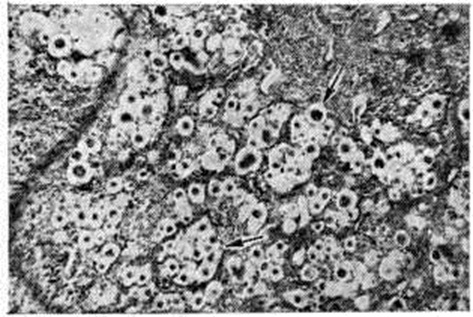

Изменения в лёгких при криптококкозе носят очаговый характер. Очаги могут быть одиночными или множественными с вовлечением в патологический процесс одной или нескольких долей лёгкого и представляют собой желатинозные уплотнённые участки диаметром до 7—10 сантиметров, не подвергающиеся казеозному некрозу, склонные к фиброзированию. При острой криптококкозной пневмонии грибки, заполняющие альвеолы, имеют округлую форму с чёткими контурами, диаметром от 5 до 20 микрометров с темным центром и широким светлым ободком. При хронический течении процесса по периферии очагов поражения развивается грануляционная ткань. Такие ограниченные, стационарные очаги называются криптококкомами (рисунок 1), по старой классификации — торулемами.

Рис. 1.

Микропрепарат криптококкомы лёгкого: скопления криптококков (указано стрелками) в ткани резецированной доли лёгкого; окраска гематоксилин-эозином; ×160.